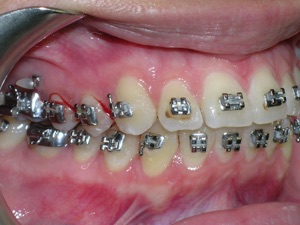

Here’s a case of crowding treated by trimming or narrowing of teeth. Also we utilized temporary anchor devices (mini screws) to help us keep the front teeth from sticking out too much.

Take a look at the braces applied as well as the trimming we did. Elastics were used from the mini screws.